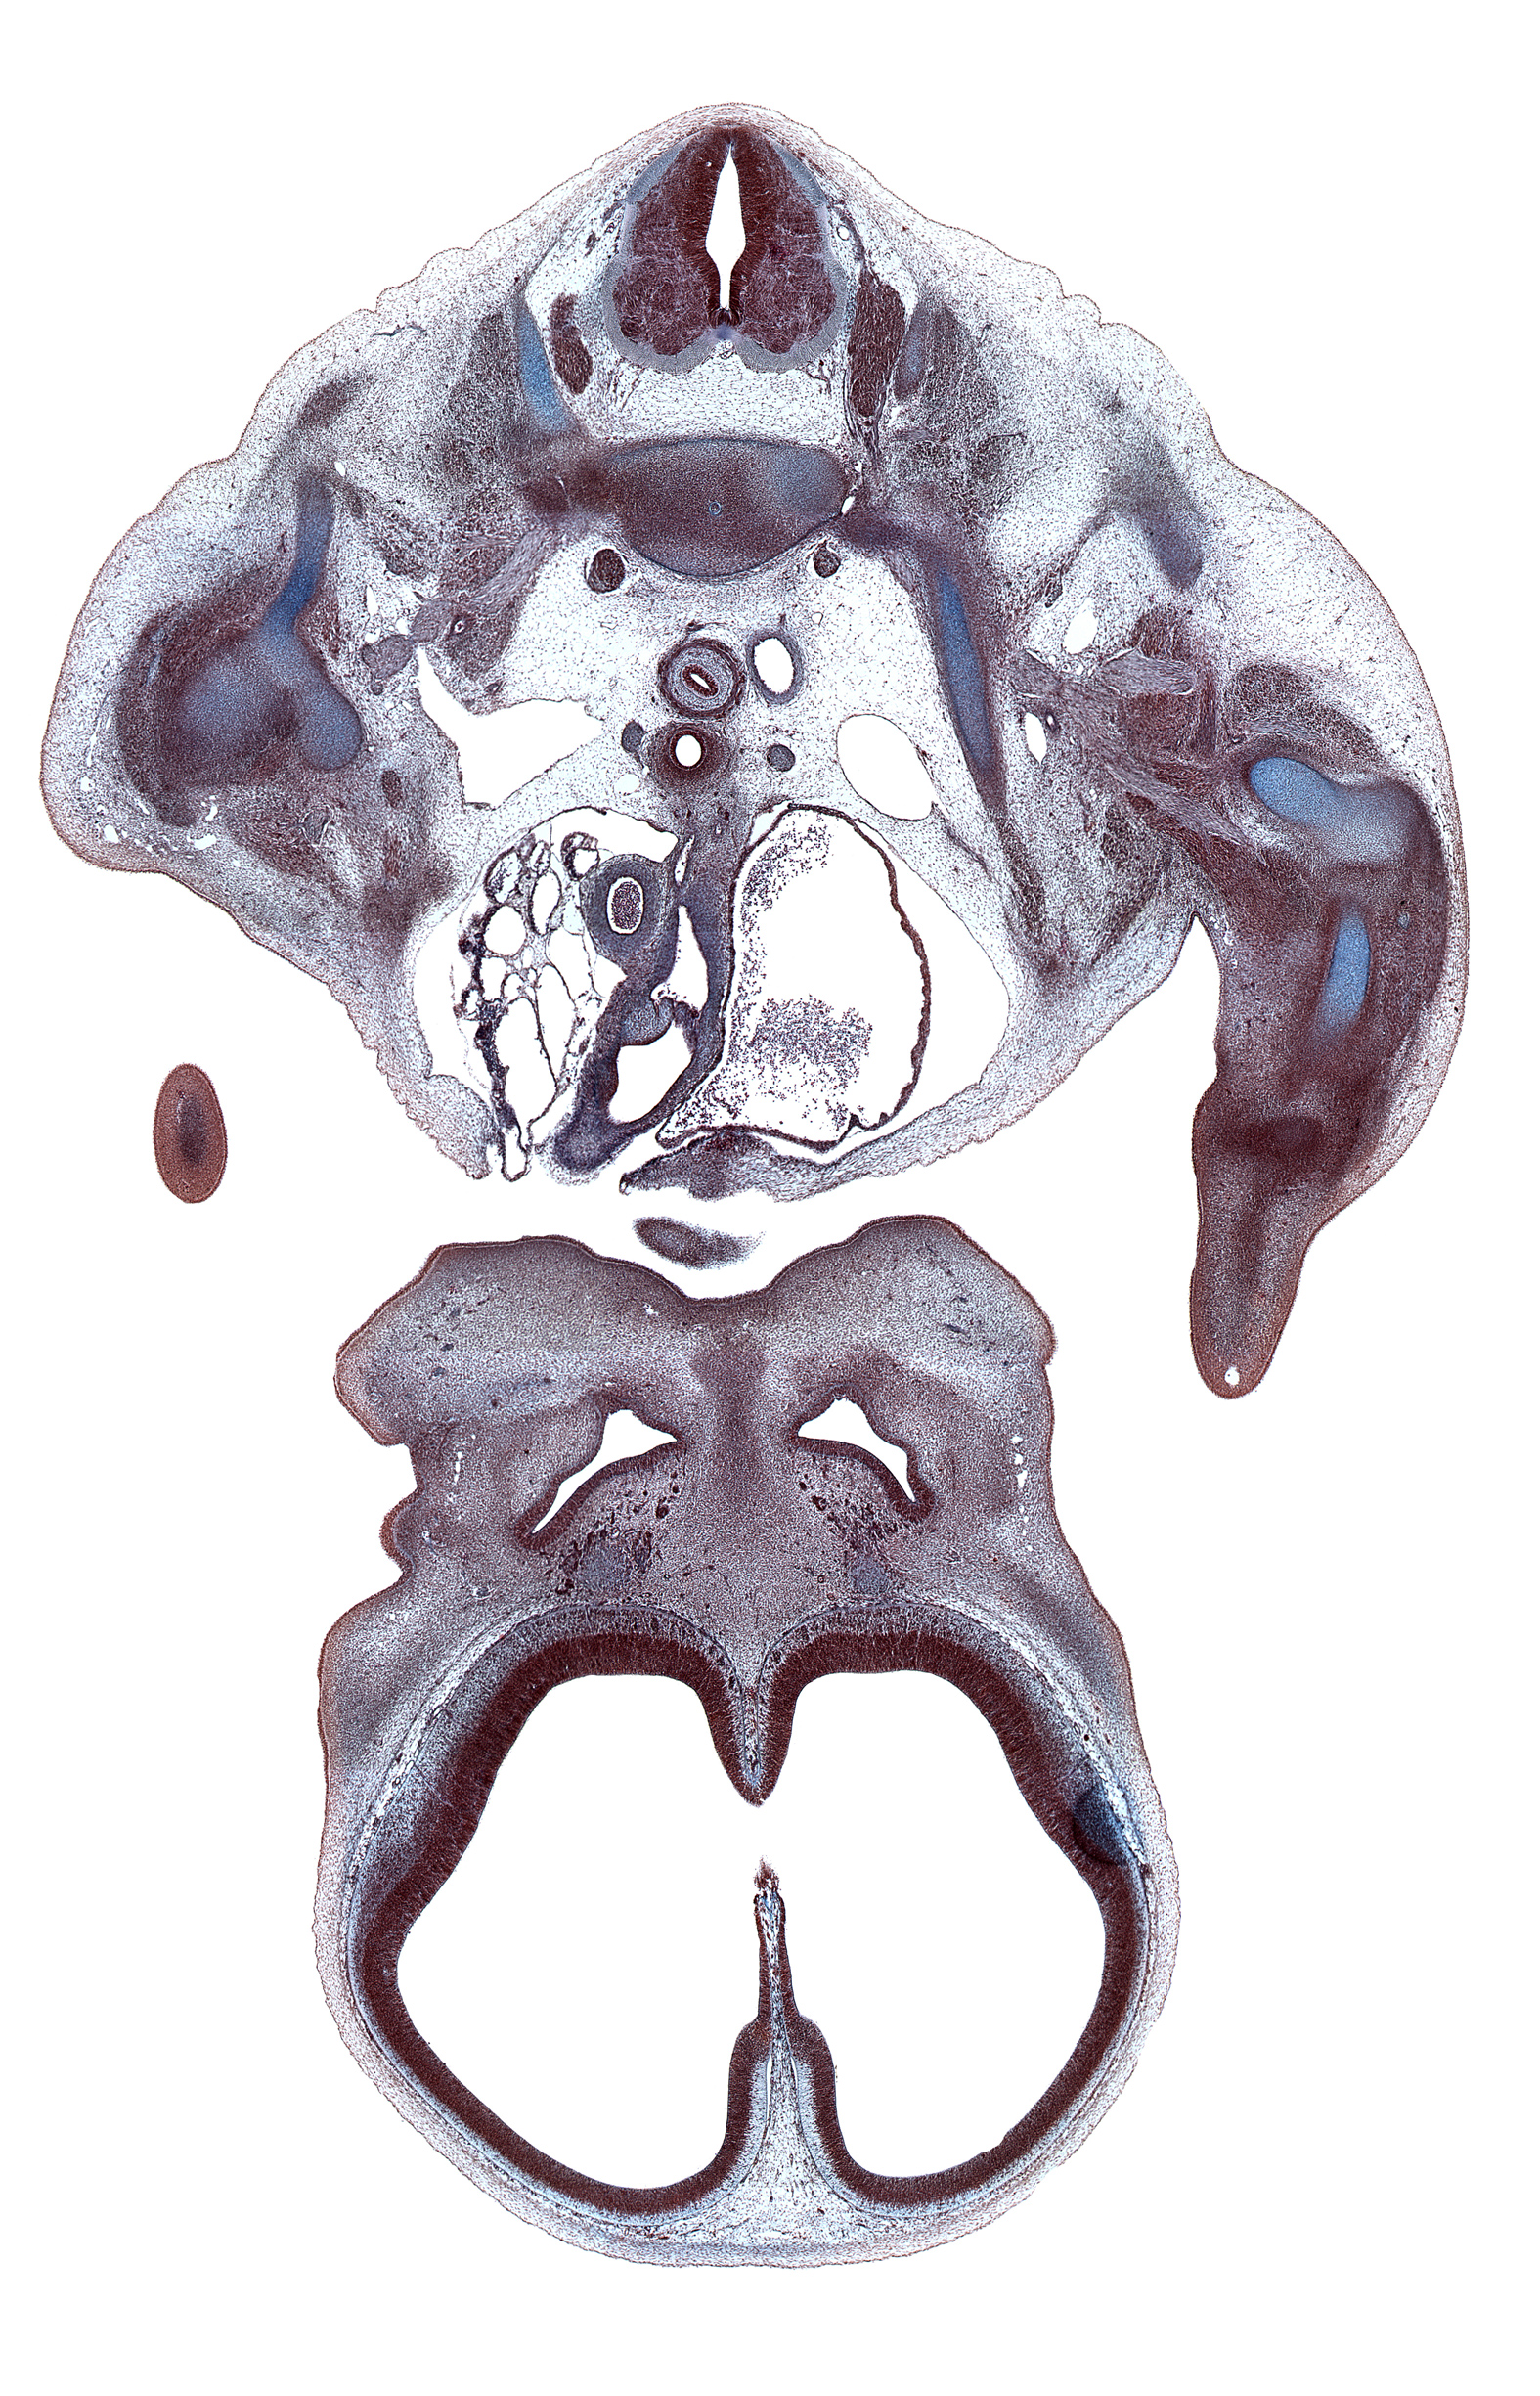

Carnegie Embryo #9325 | Location: 14-4-3

Keywords: C-7 / T-1 intervertebral disc, T-1 intercostal nerve, T-1 spinal ganglion, T-1 spinal nerve, artifact(s), ascending aorta, centrum of T-1 vertebra, cerebral vesicle (telencephalon), edge of chin, edge of interventricular foramen, frontal prominence, hippocampus, humerus, infundibulum of right ventricle, lamina terminalis, lateral ventricle, left atrium, left pulmonary artery, maxillary prominence of pharyngeal arch 1, olfactory filia (CN I), olfactory placode, pericardial cavity, primary palate, pulmonary semilunar valve, pulmonary trunk, right subclavian artery, right subclavian vein, scapula, shaft of rib 1, superior vena cava, sympathetic trunk, vagus nerve (CN X)

Source: The Virtual Human Embryo.